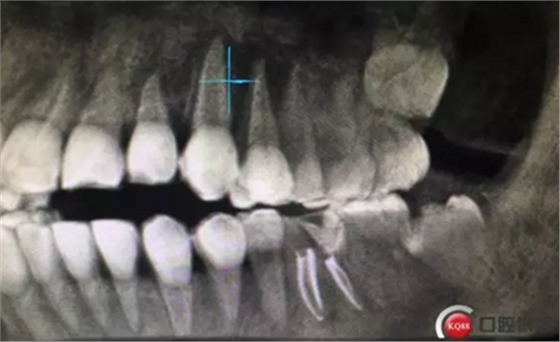

兩周后復(fù)診,完善根管治療,牙齦恢復(fù)良好,牙周探診深度最大2mm,未探及根分叉。

根管治療完成攝片

治療完成,聚羧酸鋅水門汀暫封觀察一周,后期常規(guī)根管樁全冠修復(fù)。同期16治療完成。